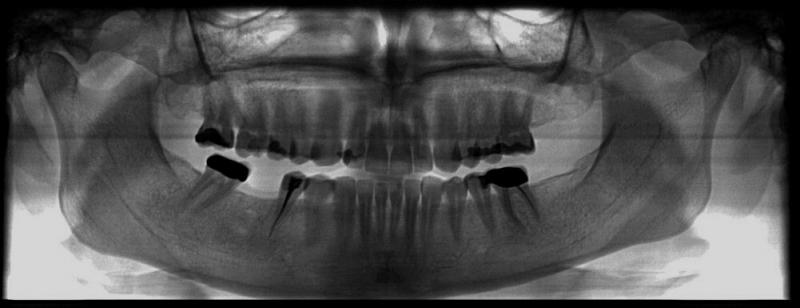

Meine Zahnärztin hat diese Eiteransammlung entfernt und Röntgenbilder (Lücke und Panorama) gemacht, welche beide unauffällig waren.

Meine Zahnärztin hat diese Eiteransammlung entfernt und Röntgenbilder (Lücke und Panorama) gemacht, welche beide unauffällig waren.

Bitte stellen sie ein Röntgen rein und senden Sie mir dei Befunde, das Geschriebene ergibt so keinen Sinn … “ohne entzündliche Anzeichen” … eine OM ist eine Entzündung …

[ATTACH=CONFIG]738[/ATTACH][ATTACH=CONFIG]739[/ATTACH]

[U]Dieses Bild wurde unmittelbar vor der Eröffnung der Eiterbeule gemacht.[/U] Ich habe auch noch eine “Nahaufnahme”, aber die lässt sich gerade einfach nicht hochladen. Da kommt immer nur so ein rotes Ausrufezeichen. Verflixt! Ich versuche es später noch mal.

Ich war inzwischen beim Kieferchirurgen (Oberarzt). Auch er meint: höchstwahrscheinlich ist nix, erst mal abwarten, ob sich da noch mal jemals irgendwas rührt. Das Röntgenbild fand er völlig undramatisch. Er meinte, die beiden Flecken in der Lücke seien halt Umbauprozesse im Knochen, das sei normal.